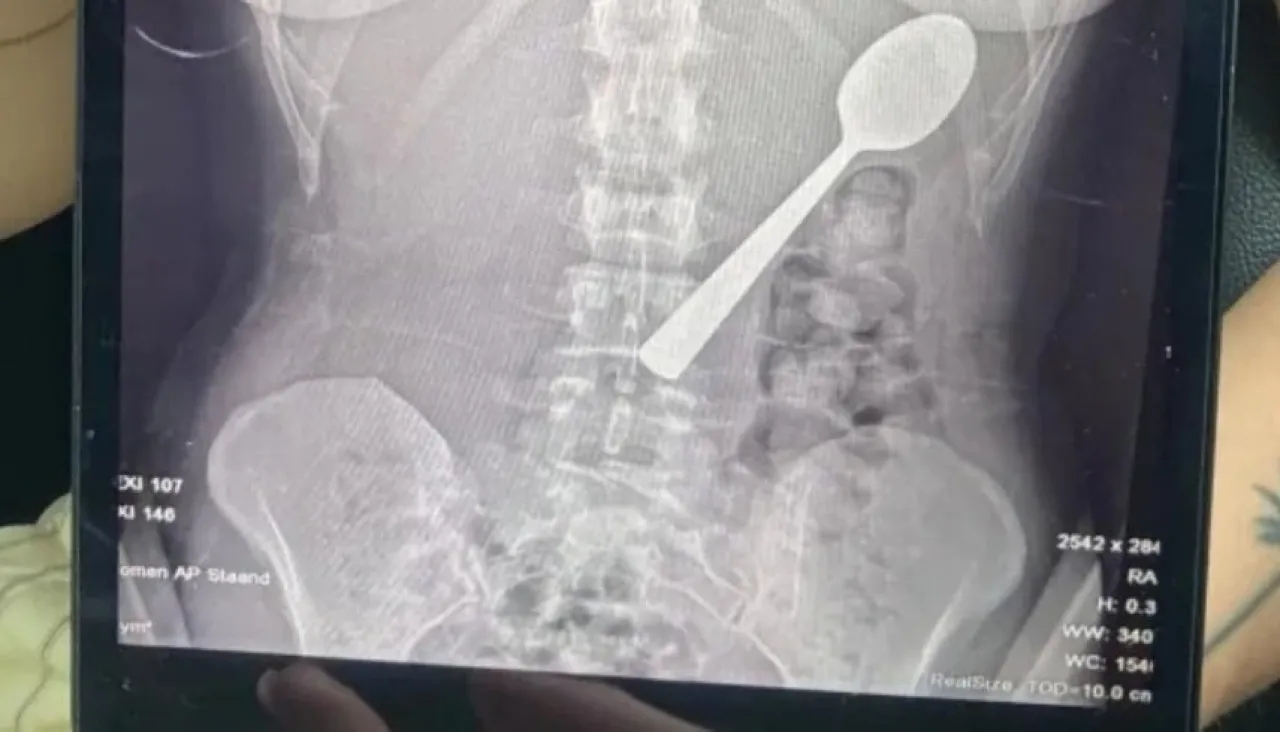

- تعرضت امرأة بلجيكية لموقف صادم بعدما ابتلعت ملعقة بطول 17 سنتيمتراً عن طريق الخطأ أثناء تناولها الطعام، وذلك بعد أن قفز كلبها على جسدها بشكل مفاجئ.

وقالت ريمي أملينكس، البالغة من العمر 28 عاماً، إنها اضطرت للاختيار بين الاختناق أو ابتلاع الملعقة، مشيرة إلى شعورها بأنها "انزلقت بسلاسة إلى معدتها".

وأضافت في تصريحات صحفية أنها كانت تجلس على الأريكة أثناء تناول الزبادي، وعندما قفز كلبها من نوع "هنغاريان فيزلا" المعروف بنشاطه، تفاجأت بشكل كبير ما أدى إلى انحشار الملعقة في حلقها بالخطأ،  فحاولت إزالتها بيدها، لكن الموقف كان سريعاً جداً ولم يكن أمامها سوى ابتلاعها لتجنب الاختناق.

وبعد تناول العشاء، أدركت خطورة الموقف، وذهبت إلى الأطباء الذين أبلغوها أن الملعقة كبيرة جداً لتخرج طبيعياً، ما استدعى انتظار إجراء منظار معدة.

وخلال هذه الفترة، شعرت المريضة بحركة الملعقة داخل جسدها، وأصيب جسدها بالانتفاخ وشعرت بالغثيان وصعوبة في النوم.

وأُزيلت الملعقة بعد يومين تحت التخدير الموضعي، حيث اضطر الأطباء لتدويرها داخل المعدة، ما تسبب في نزيف بسيط، وأكدت ريمي أن الحادث لم يترك أي أضرار دائمة، لكنها تعرضت لالتهاب في الحلق ونزيف في المعدة طفيف وحساسية لبعض الوقت.